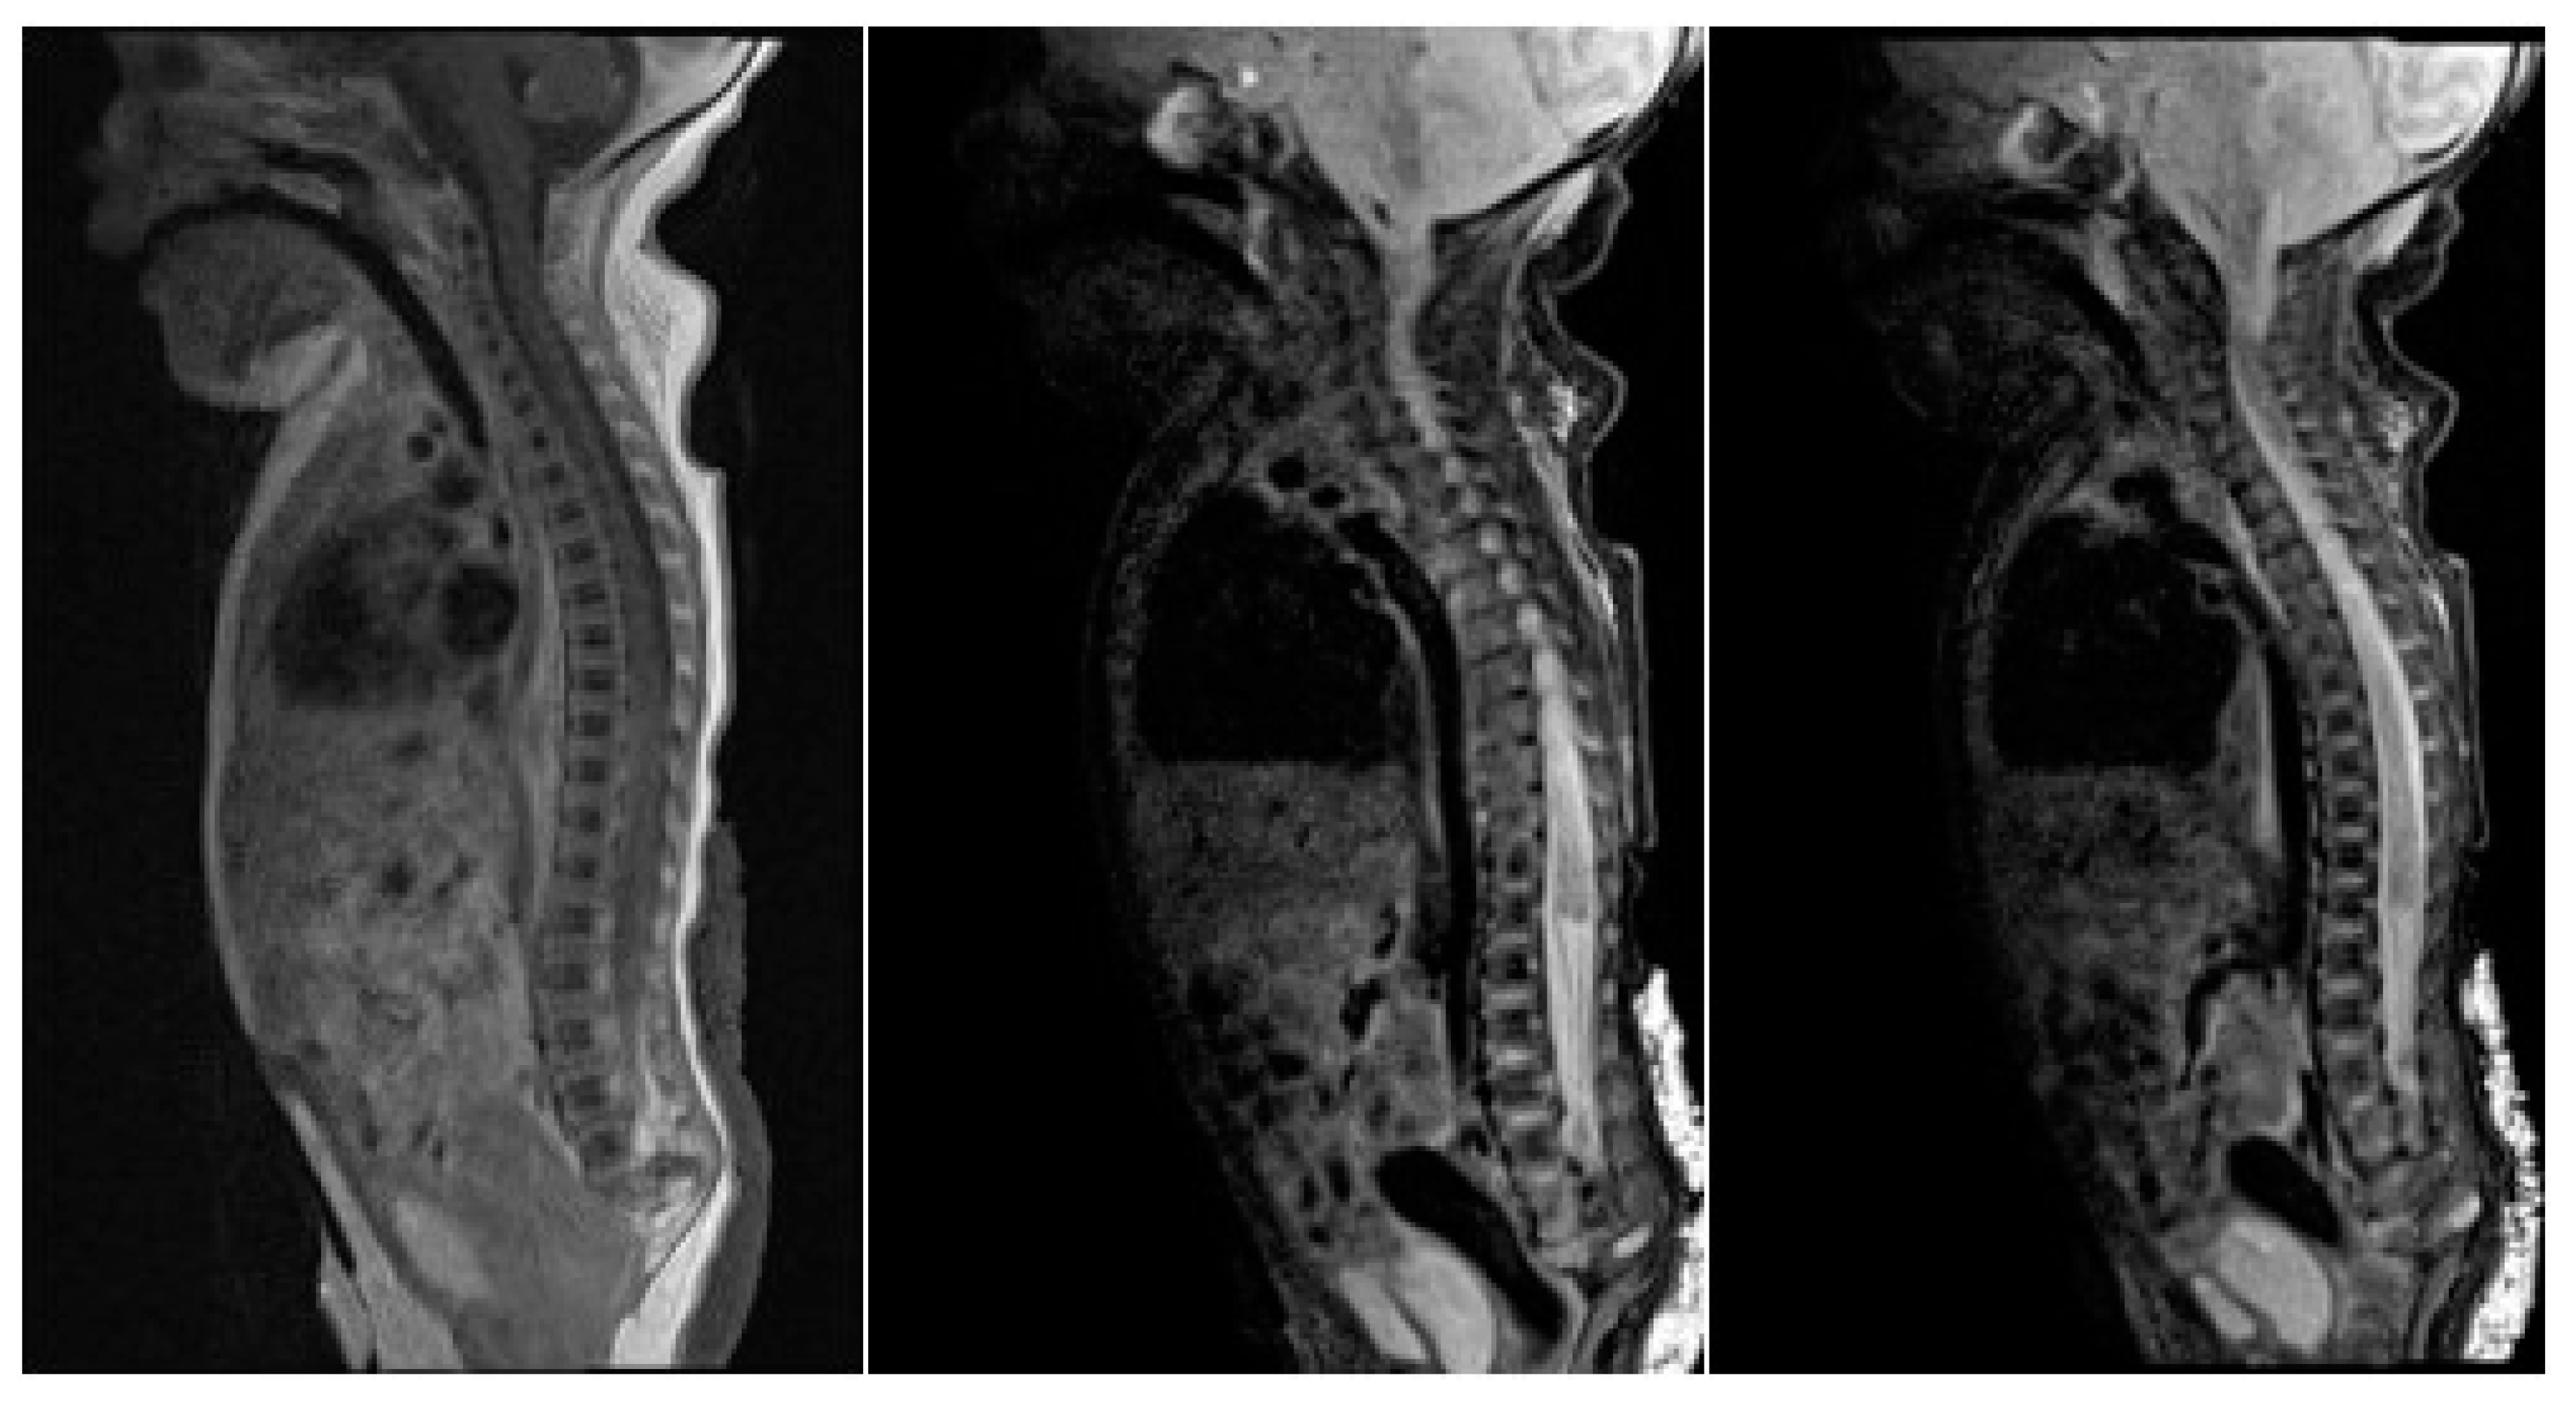

2. Case Presentation